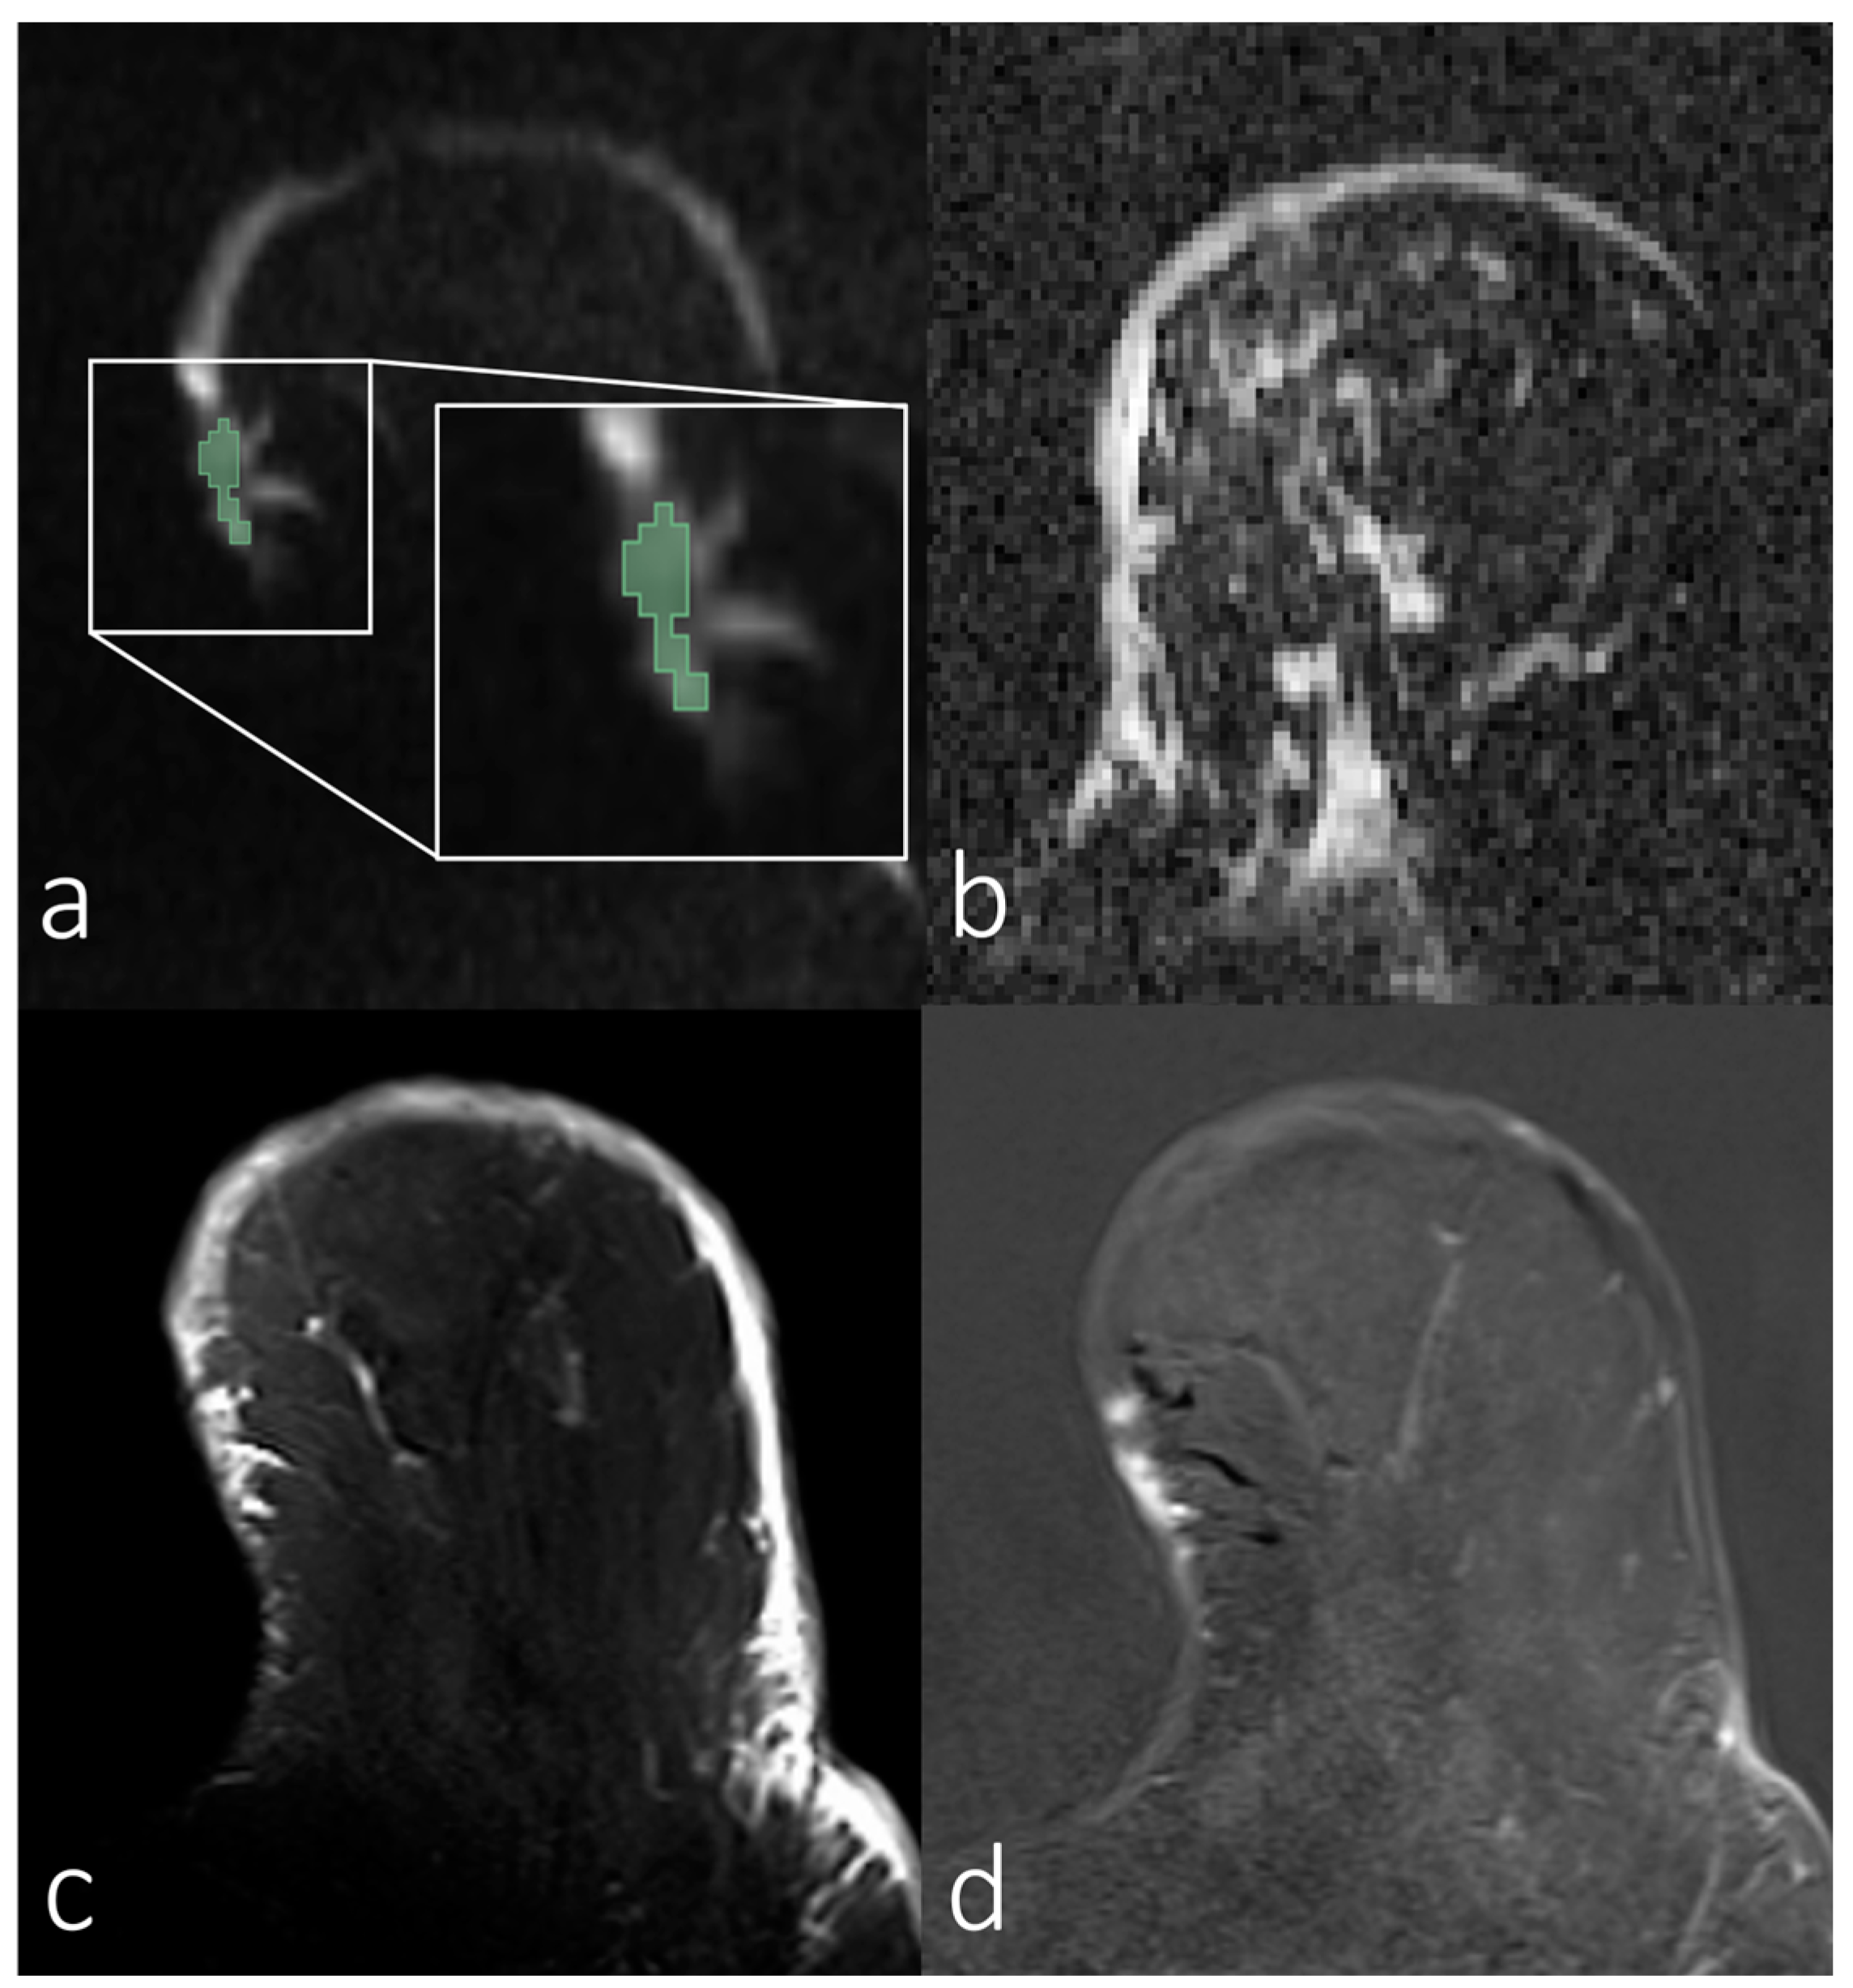

3.2. Analyses of First-Order Statistics Using the ADC

3.3. Evaluation of SNR in the Skin for Assessing ADCs in Skin Pathologies